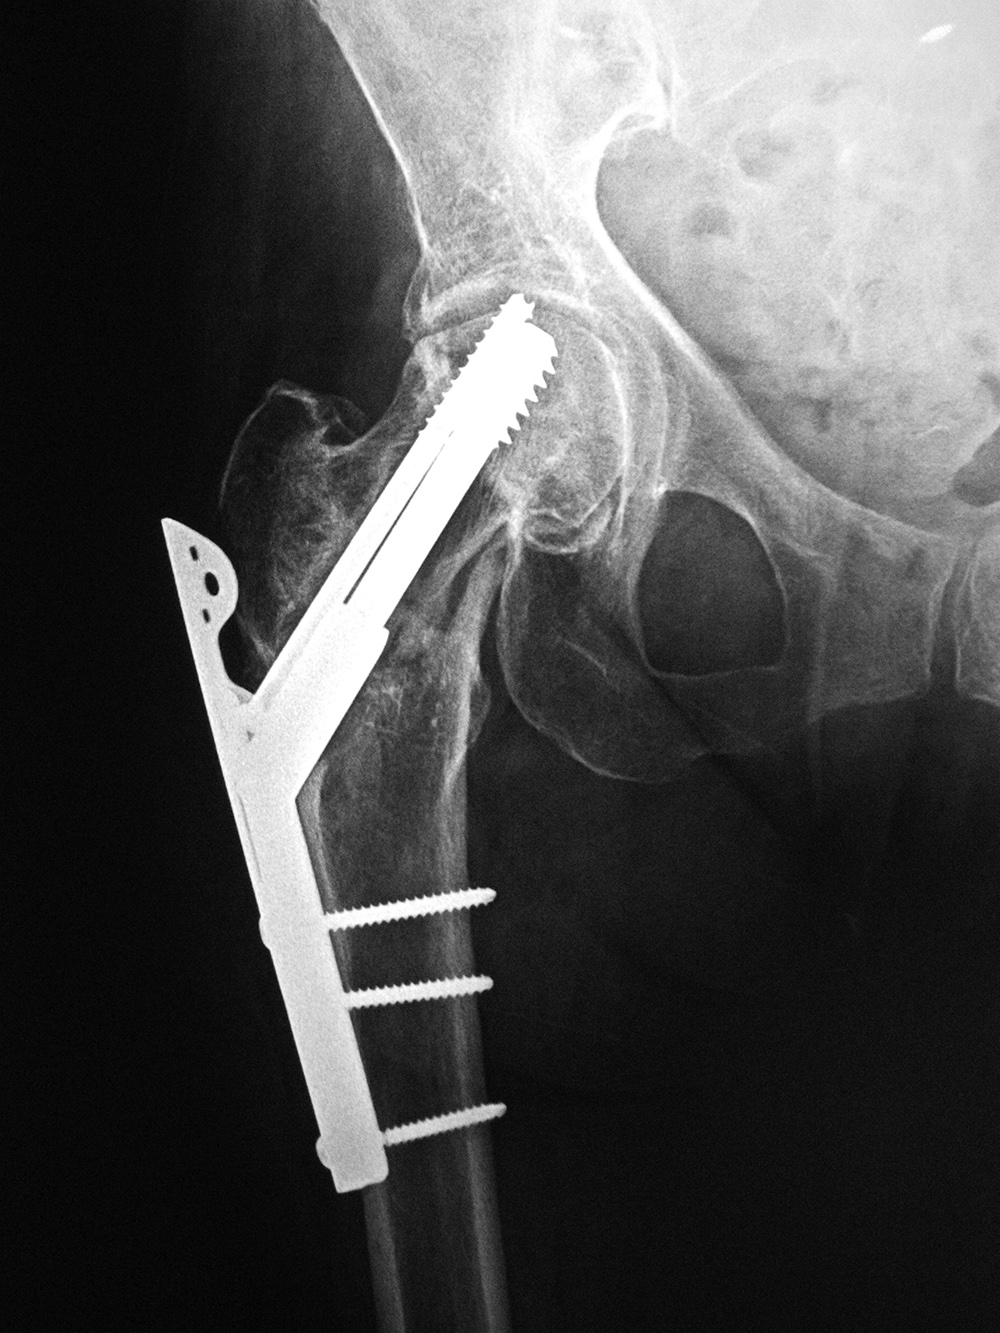

Intraoperative fixation of an intertrochanteric fracture demonstrates a cephalomedullary device with the tip of the cephalic screw positioned too short and very inferior in the neck (very large tip-apex distance). |

Subsequent fracture fixation failure observed as the head and neck segment of the femur flexed 90 degrees with cut-out of the screw approaching the hip joint. |